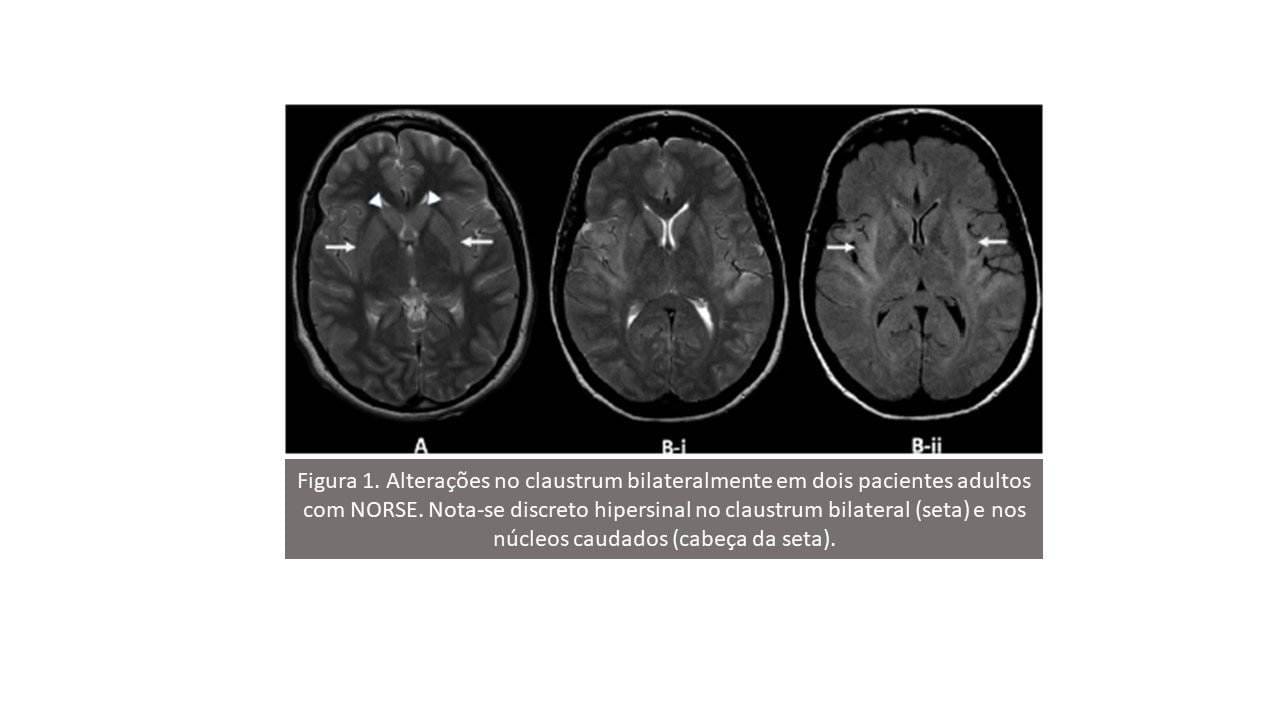

Em seis crianças com FIRES criptogênica, a ressonância magnética do crânio era normal no início da doença (dias 0–2 de estado de mal epiléptico), mas logo (dias 3–10) mostrou alto sinal no claustro (‘claustrum sign’) em T2 / FLAIR e na difusão, com ADC normal e sem realce pelo contraste.

Este aspecto de imagem tende a reduzir, retomando o aspecto normal depois que o status epilepticus diminui.

Houve outros casos com alterações precoces do claustro, inclusive em adultos (FIGURA 1). As alterações claustrais, no entanto, foram relatadas como infrequentes, ocorrendo em 3/39 casos em uma série recente.